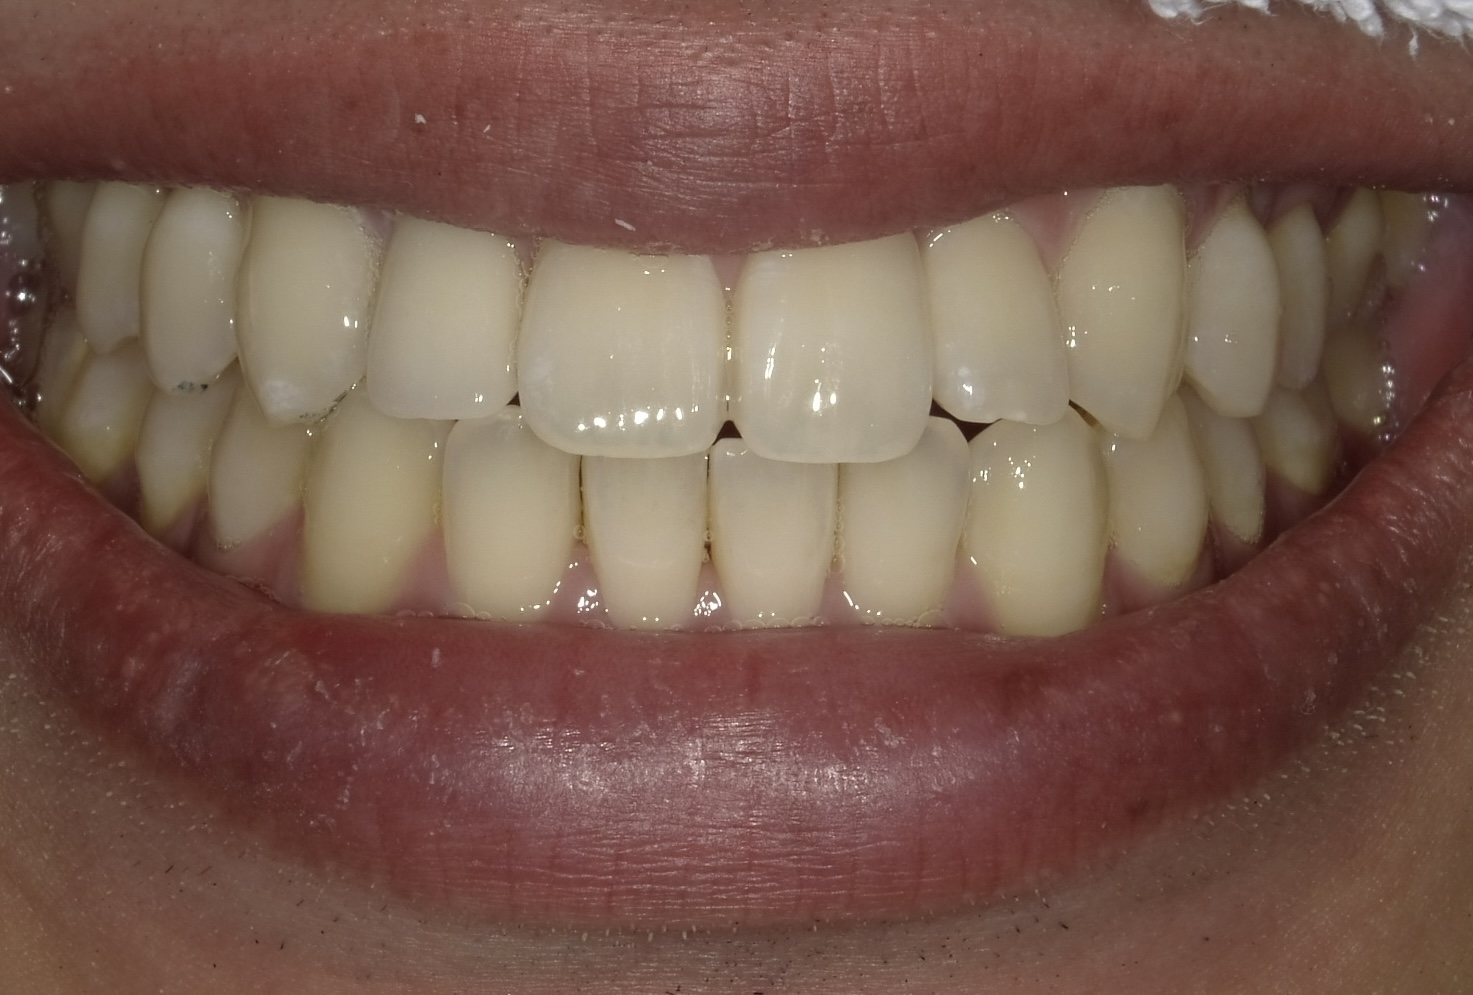

【After】セラミッククラウン装着。どこを治療したか分からないほど馴染んでいます。

- 治療方法:セラミッククラウン法 + オフィスホワイトニング

- 治療期間:約1ヶ月 / 費用:¥220,000(税込)

- リスク:歯を削る必要があります。